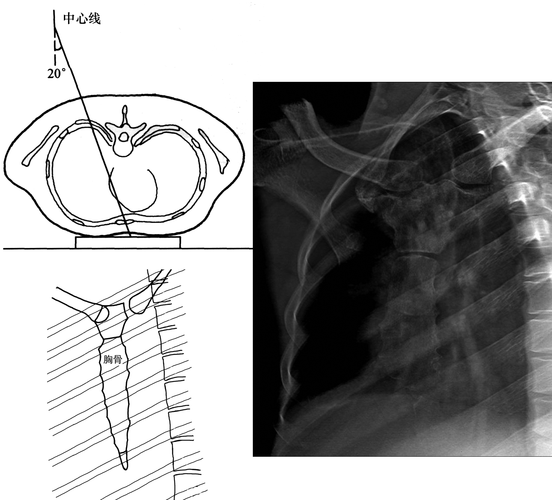

收藏x线摄影技术胸部正侧位摄影标准摆位图文解析